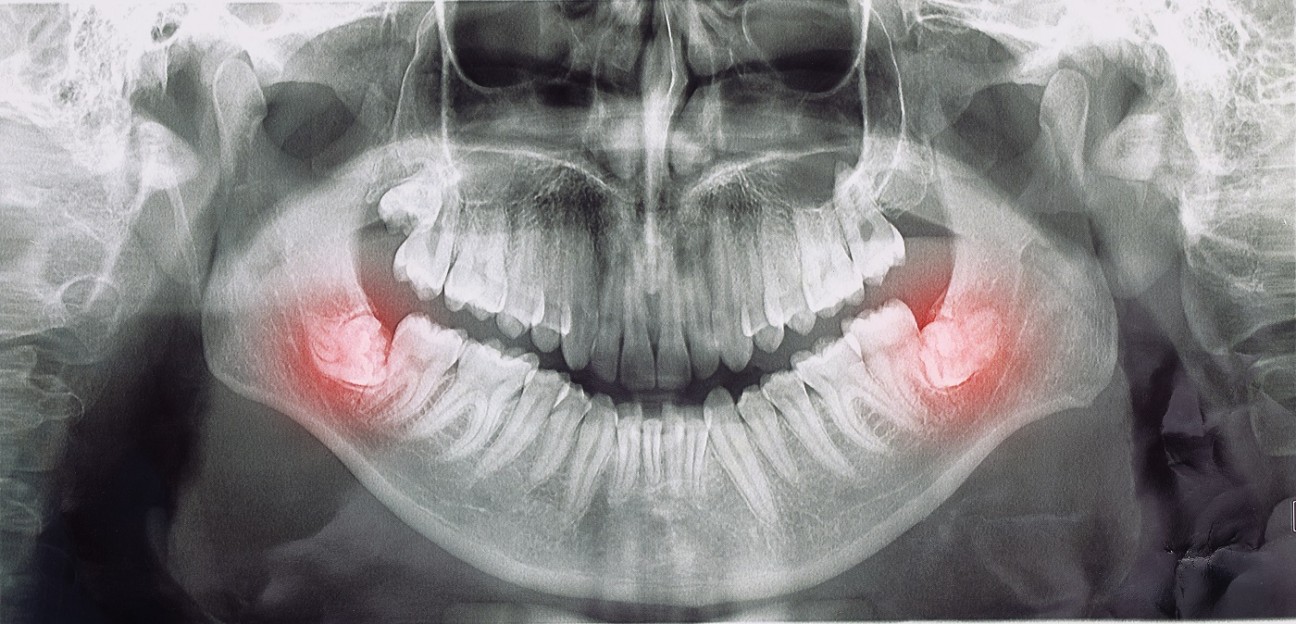

20 Yaş Dişi Tedavileri (Gömülü / Yarı Gömülü): Cerrahi Çekim ve İyileşme Süreci Yönetimi

20 yaş dişleri, ağız sağlığında sıkça karşılaşılan ve bazen gömülü ya da yarı gömülü olarak konumlanabilen dişlerdir. Bu durum, enfeksiyon, ağrı ve komşu dişlere zarar gibi problemlere yol açabileceğinden, profesyonel tedavi gerektirebilir. Tedavi sürecinde, cerrahi çekim ve sonrasında dikiş / iyileşme süreci yönetimi kritik rol oynar.

Cerrahi çekim, gömülü veya yarı gömülü 20 yaş dişlerinin güvenli ve kontrollü bir şekilde çekilmesini sağlayan işlemdir.